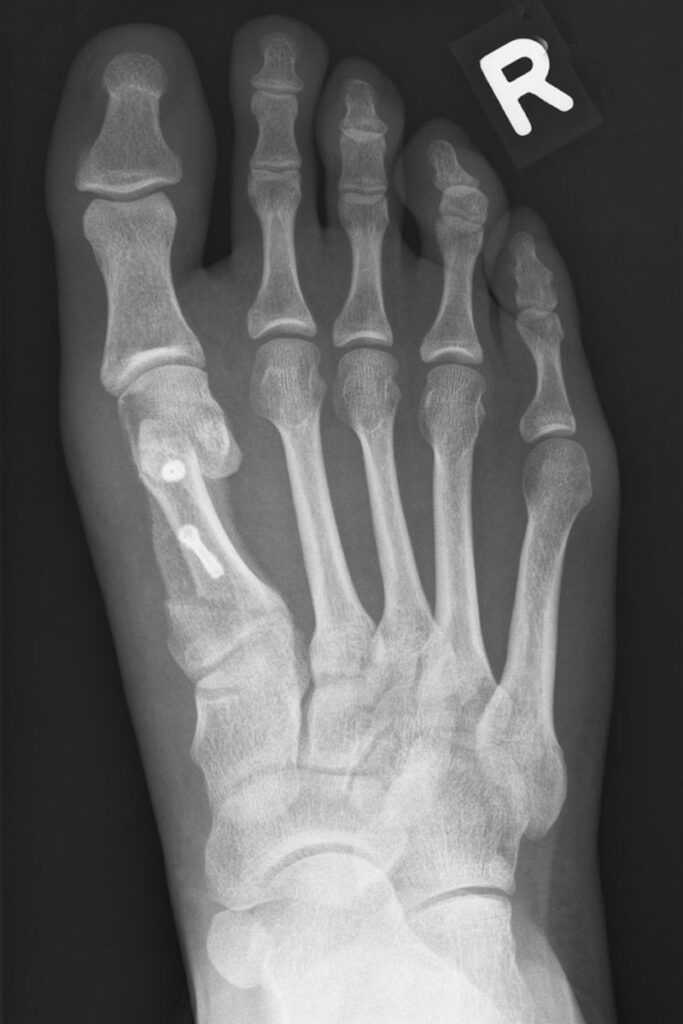

Röntgen Fußchirurgie

ausgeprägter Hallux Valgus